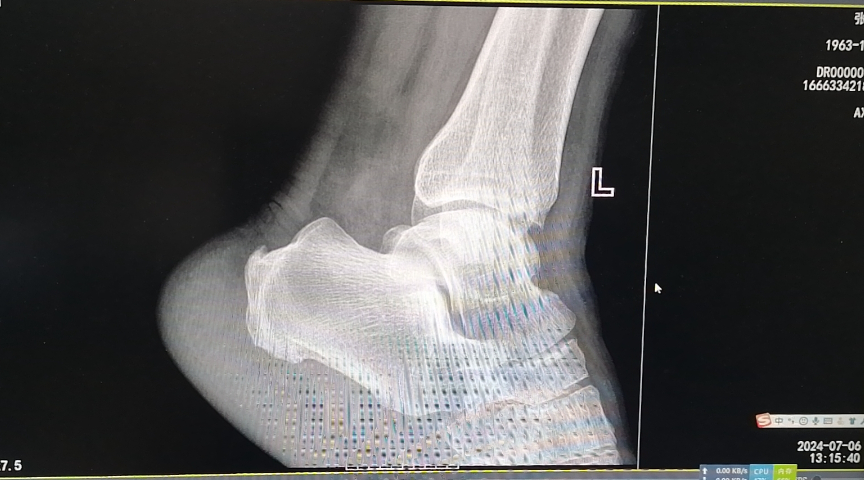

张大叔3年前无明显诱因出现左足底疼痛,行走时疼痛加重,休息后可缓解,近1个月来上述症状逐渐加重,左足跟部为重,活动时加重,休息后缓解,曾用云南白药气雾剂,左底喷涂,效果欠佳。近日因疼痛难忍,无法正常行走,影响正常生活,门诊就诊,行左足跟骨正侧位片示:左跟骨骨刺。为求进一步治疗,以“足底跟痛症”收治入院。

(入院影像结果)